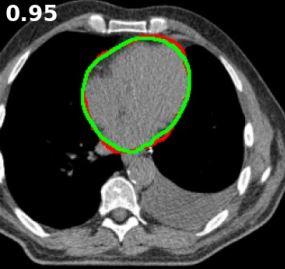

2. UDBRNet.gif

UDBRNet: A novel uncertainty driven boundary refined network for organ at risk segmentation

Riad Hassan, M. Rubaiyat Hossain Mondal, and Sheikh Iqbal Ahamed

PLOS ONE, Jun 2024